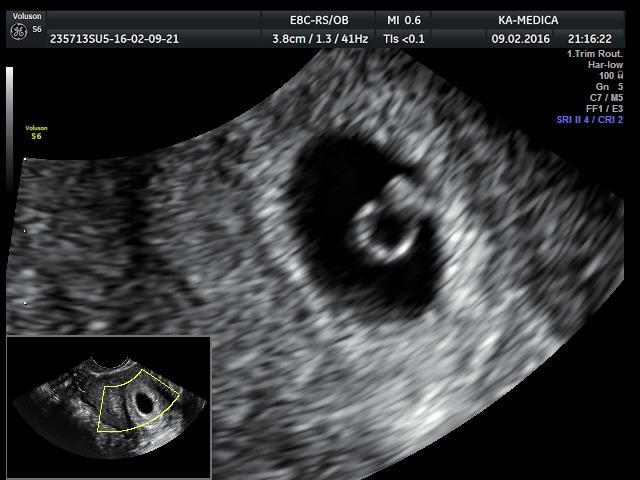

Kochana ja w 5+5 widoczny tylko pęcherzyk ciążowy i pęcherzyk żółtkowy teraz czeka mnie wizyta 2 lutego i zobaczymy czy coś więcej widać . 💁‍♀️ I ja z kolei biorę luteinę bo w dzień wizyty miałam brązowe plamienia 🙈

No wlasnie, z racji ze bylam pierwszy raz tak wczesnie na usg (5+5) to powiedzcie mi co oznacza taka jakby bańka w pecherzyku? Dokladnie widzialam pecherzyk i w srodku taka bańka okrągła... u was to jakos inaczej wyglada...

Tak to mniej wiecej wygladalo, ale sam ten okragly babelek...nigdy nie uswiadczylam takiego widoku, zastanawiam sie czy jest ok...Zobacz załącznik 1233036

Bardzo ładny pęcherzyk żółtkowy. To dobry znak, bo najprawdopodobniej po 1-2 dniach pojawi się zarodek. Wygląda na to, że narazie wszytko rozwija się książkowo jak na ten etap ciąży. Myślę, że na najbliższej wizycie zobaczysz serduszko ✊✊✊